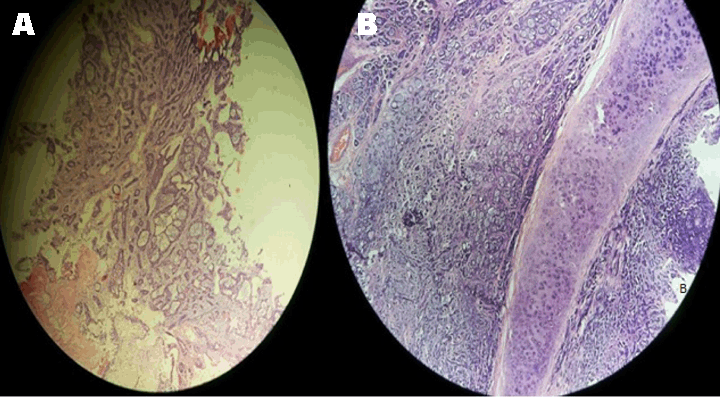

On postoperative day (POD) 1 the patient developed respiratory distress with air bubbling in the mediastinal drain. Check bronchoscopy showed a gape in suture line in posterior wall of trachea along the left lateral aspect over a region of 1–2 stitches. After a multidisciplinary meeting (MDM), it was decided to reintubate the patient to reduce airway pressures and the patient was kept on a T-piece with spontaneous breathing. The bubbling in the drain stopped post-intubation. On POD 3 after a repeat MDM patient extubated. On POD 5 the patient shifted out of ICU with full Ryle's Tube feeds. On POD 7 check bronchoscopy done suggestive of granulation tissue noted over the gaped area. Rest of the suture line was normal. With symptomatic improvement and serial chest X-rays suggestive of reduction in mediastinal widening patient discharged on POD 14. Final histopathology report confirmed adenoid cystic carcinoma of the trachea with negative margins with no lymphovascular emboli or perineural invasion and negative lymph node (Figure 4A-B). Postoperative adjuvant radiotherapy of 56 Gy in 28 fractions for 46 days given to the tumor bed with three-dimensional conformal radiation therapy. She is on six monthly follow-ups with check bronchoscopy and annual CT scan. The patient remains asymptomatic with normal check bronchoscopy (Figure 5) and CT scan at 18th month post-procedure.

Figure 4: Microphotograph showing typical adenoid cystic carcinoma pattern with tracheal cartilage (A) At 200x heterogeneous growth patterns with cribriform subtype is predominant (B) At 400x basaloid appearance with hyperchromatic nuclei and eosinophilic cytoplasm with tracheal cartilage.